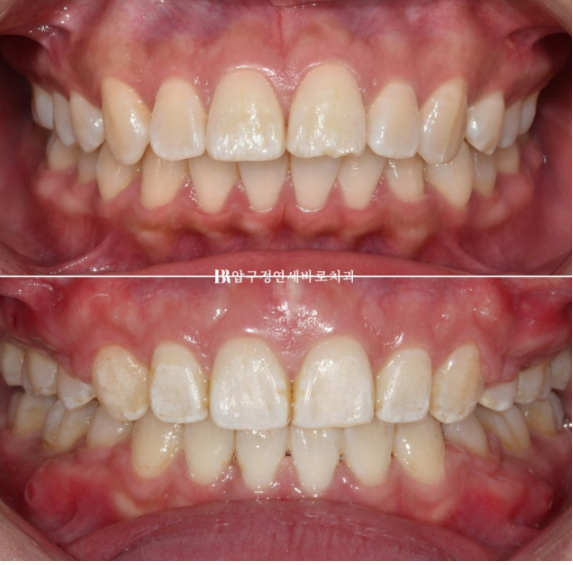

23.02~24.09

치료기간은 총 1년 7개월입니다.

전 후 정면 스마일 사진입니다.

좌우 입꼬리 안쪽에 원래 없던 입동굴이 생겼습니다.

너무 크지 않은 적절한 입동굴은 미소심미에 중요합니다.

또 한가지, 미소심미에서 빼놓을 수 없는 것은 스마일라인입니다.

스마일라인은 윗니 끝단을 이은 선을 말합니다.

이것이 아랫입술과 평행해야 웃을 때 아름답습니다.

아랫입술에 비하여 너무 편평해서 일자였던 스마일라인이 아랫입술에 평행하게 동그란 모양으로 바뀌었습니다.

입술부전증이 해결되어 이제 입술에 힘을 빼도 자연스럽게 다물어집니다.